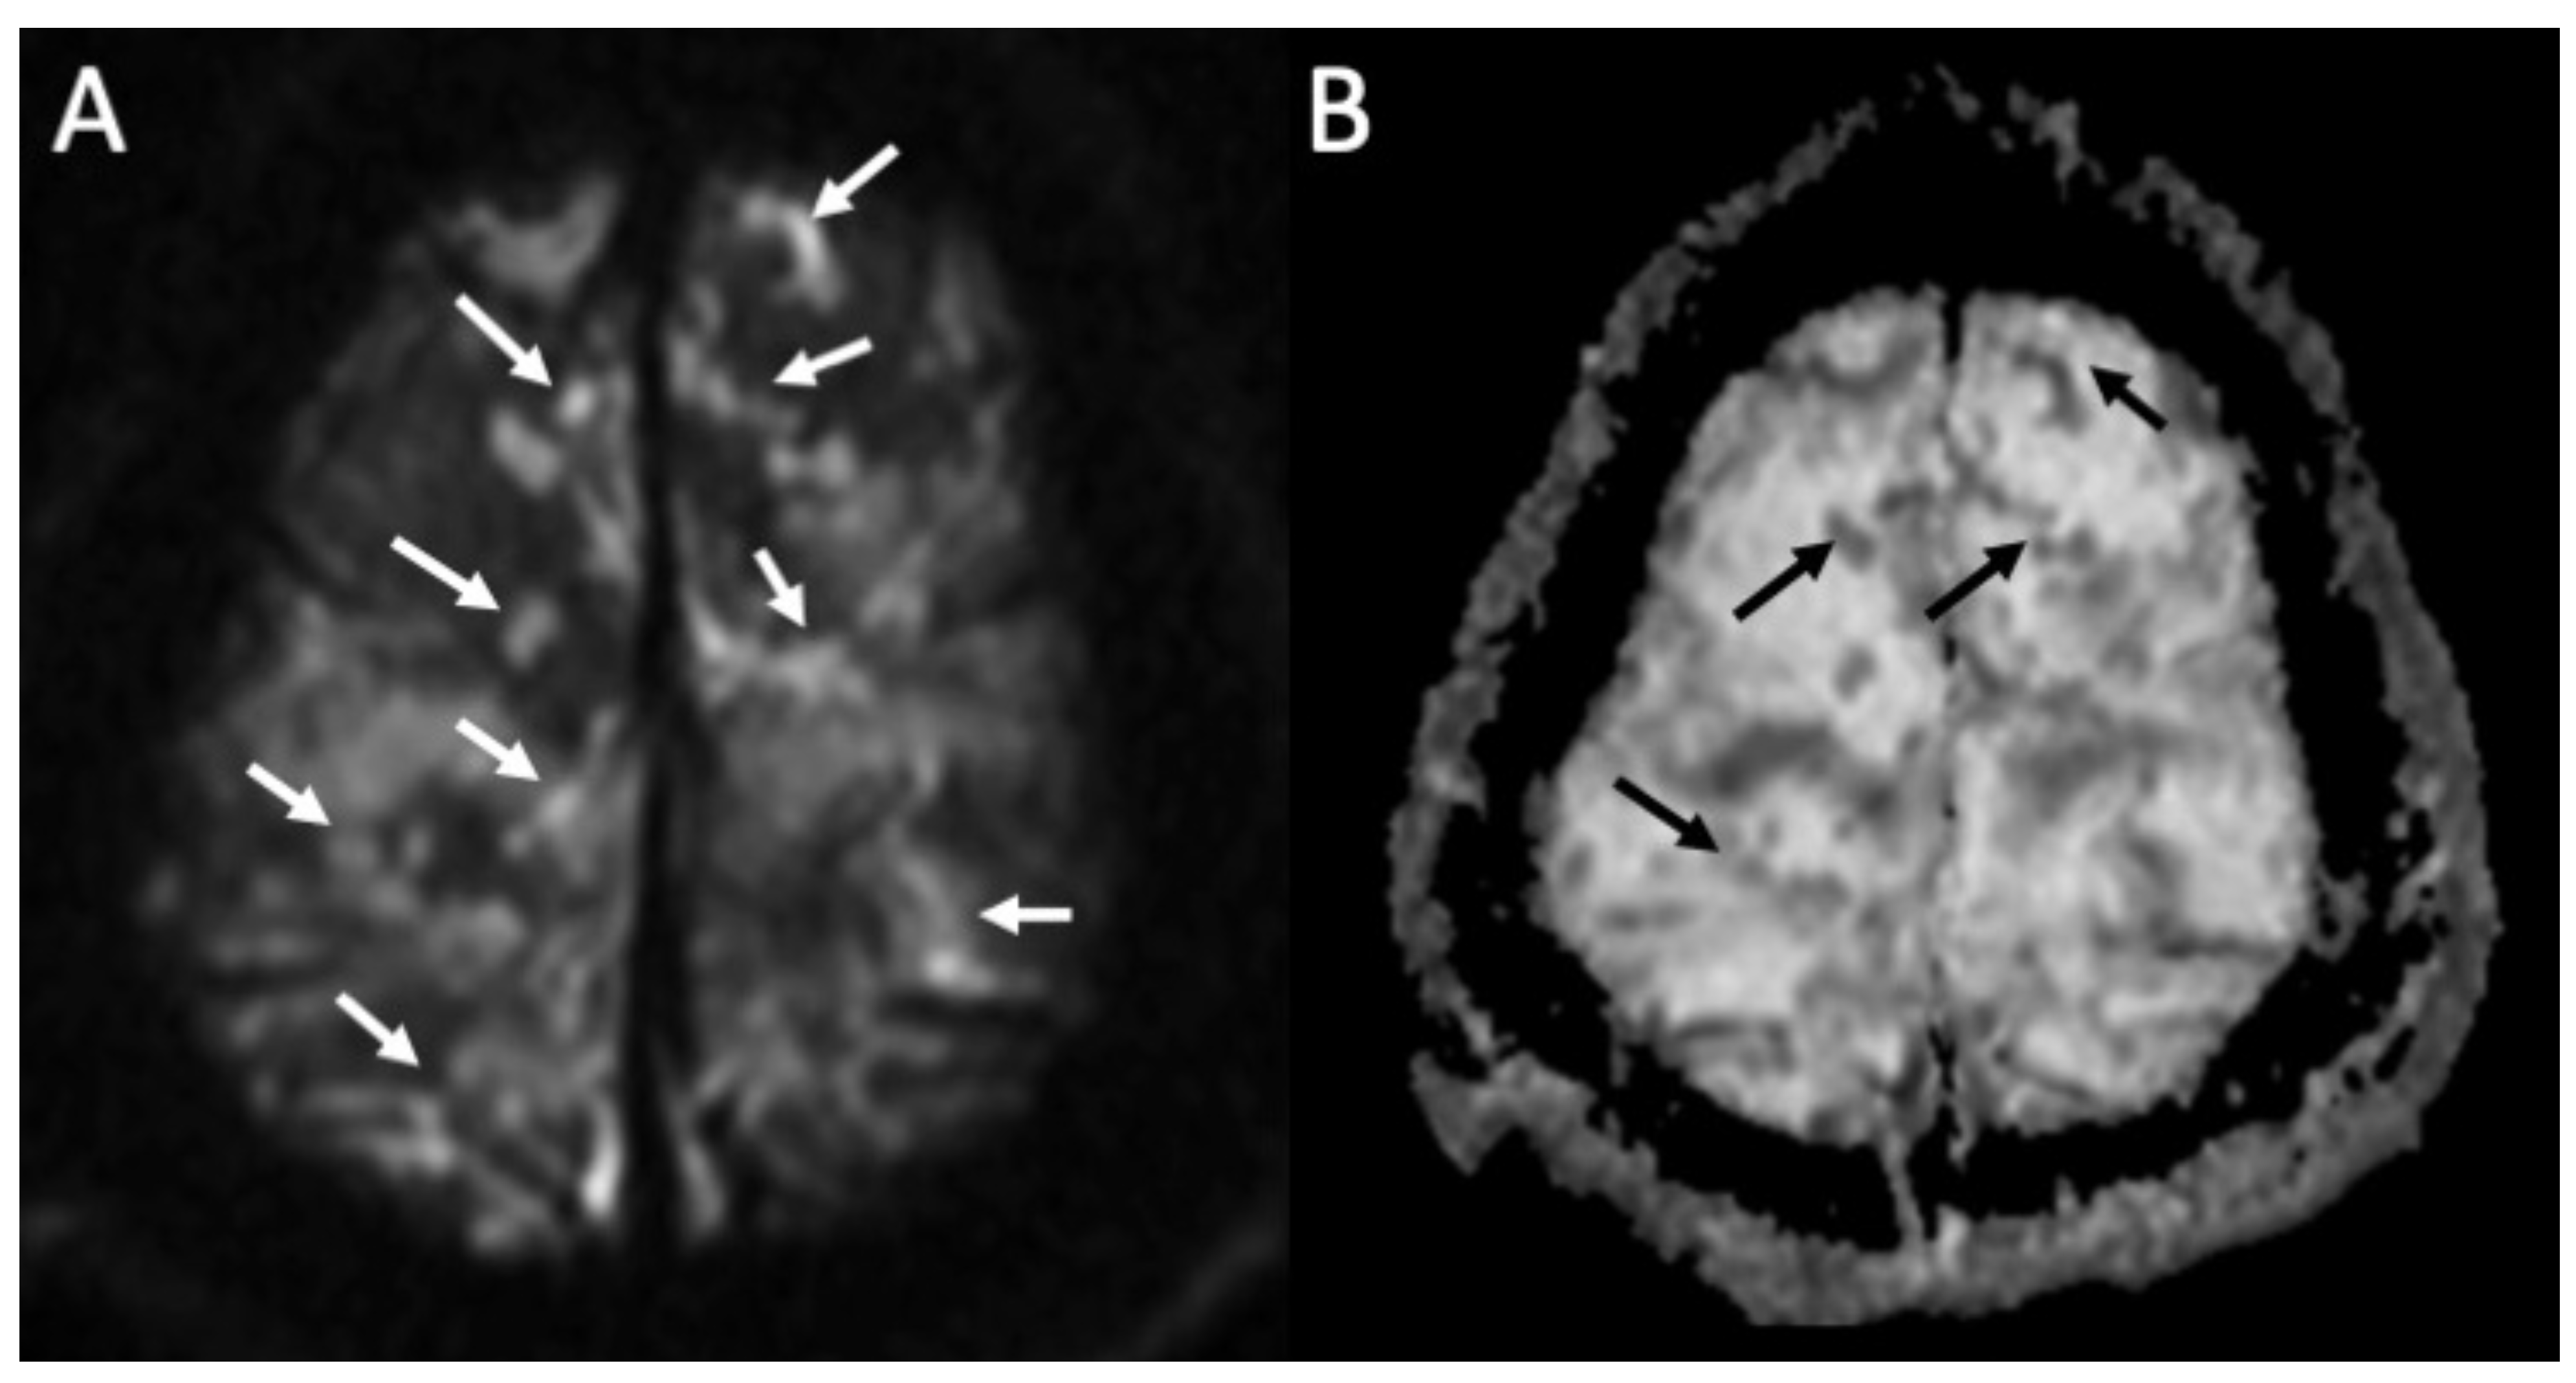

Figure 2.

Axial DWI (A), ADC (B) shows multiple foci of restricted diffusion in the subarachnoid spaces at convexity bilaterally (arrows in A,B) in a patient with newly diagnosed Streptococcus Pneumoniae meningitis.